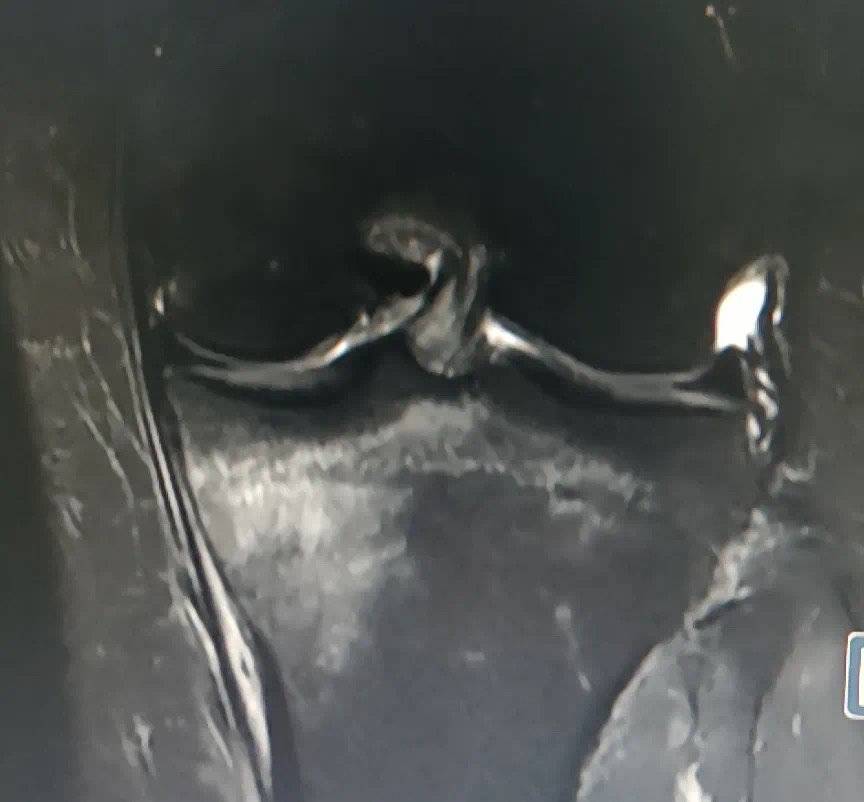

丁女士胫骨上端疲劳骨折图 。 医院供图

到成都市第一人民医院检查后 , 医生考虑丁女士为胫骨上端疲劳骨折!丁女士起初怎么都不敢相信这个结果 , 后面经膝关节磁共振检查明确 , 丁女士很困惑 , 不就是跳个绳吗 , 怎么还骨折?那怎么办呢?成都市第一人民医院骨科运动医学门诊陈志超医生建议:疲劳骨折也是一种骨折 , 因此一样要扶拐行走 , 1月内伤肢避免负重 , 避免进一步损伤受伤侧肢体 。 一个月复查一次 , 可以做适当物理治疗 , 促进骨折愈合 。